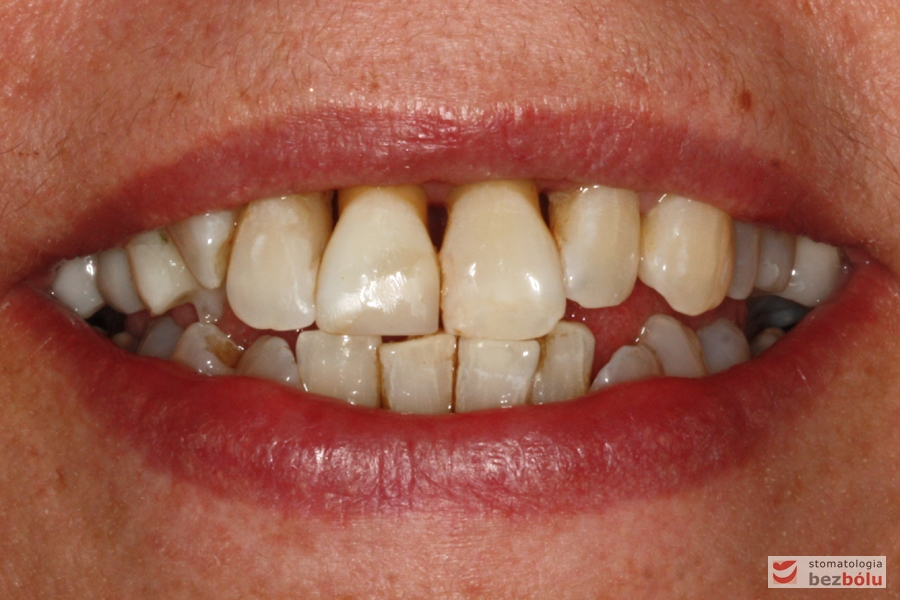

Usta w średnim uśmiechu - trójkątne przestrzenie między zębami w szczęce

Usta w średnim uśmiechu – trójkątne przestrzenie między zębami w szczęce